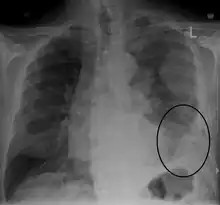

![]() | |

| CT scan showing a left sided mesothelioma with an enlarged mediastinal lymph node | |